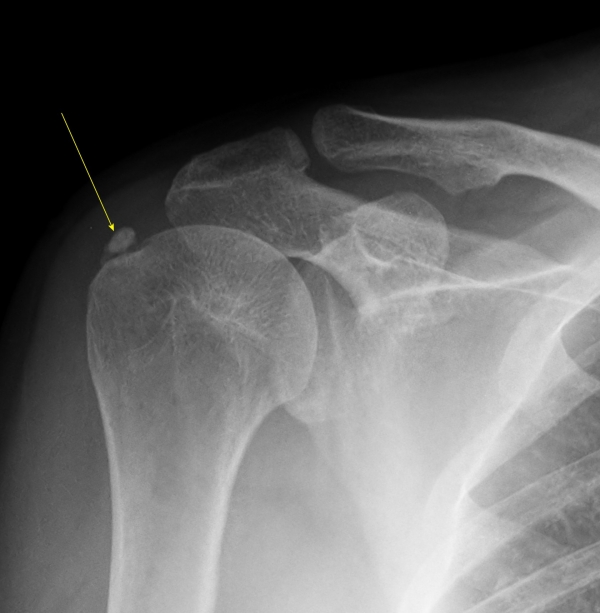

2Â÷(¾à 1°³¿ù ÈÄ) ¹æ»ç¼± °Ë»ç¿¡¼­ ¼®È¸°¡ °üÂûµÇÁö ¾ÊÀ½(»çÁø 6).